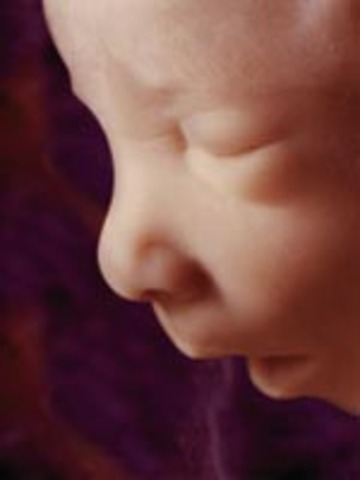

Your baby now weighs about 4 3/4 pounds (like your average cantaloupe) and is almost 18 inches long. Her fat layers — which will help regulate her body temperature once she's born — are filling her out, making her rounder.

• week 36

week 36

Your baby is still packing on the pounds — at the rate of about an ounce a day. She now weighs almost 6 pounds (like a crenshaw melon) and is more than 18 1/2 inches long.